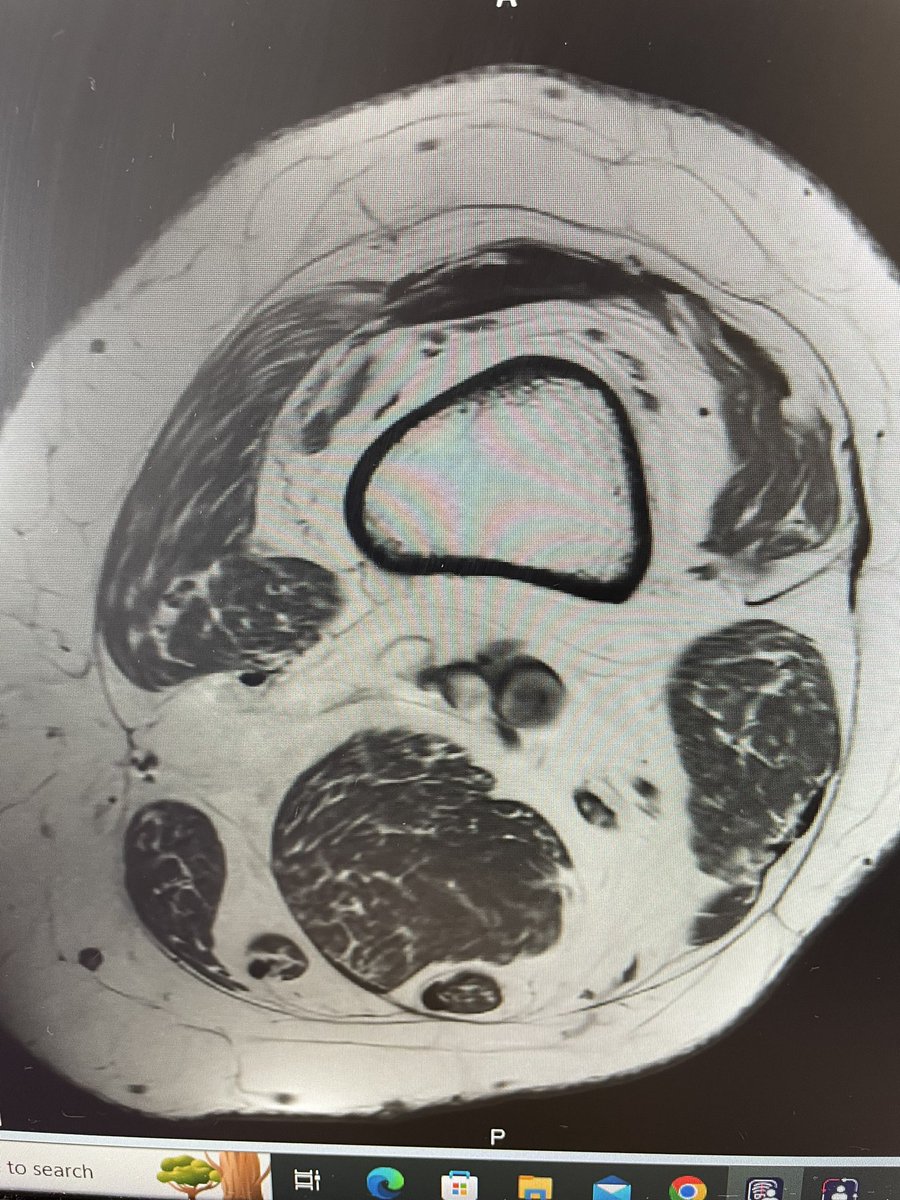

The distal thigh of a 40 something. Imagine losing this much muscle mass already and being able to remain active into your 70s and beyond. It should be very hard to imagine. Because they won’t be.

The distal thigh of a 40 something.

Imagine losing this much muscle mass already and being able to remain active into your 70s and beyond. It should be very hard to imagine. Because they won’t be.